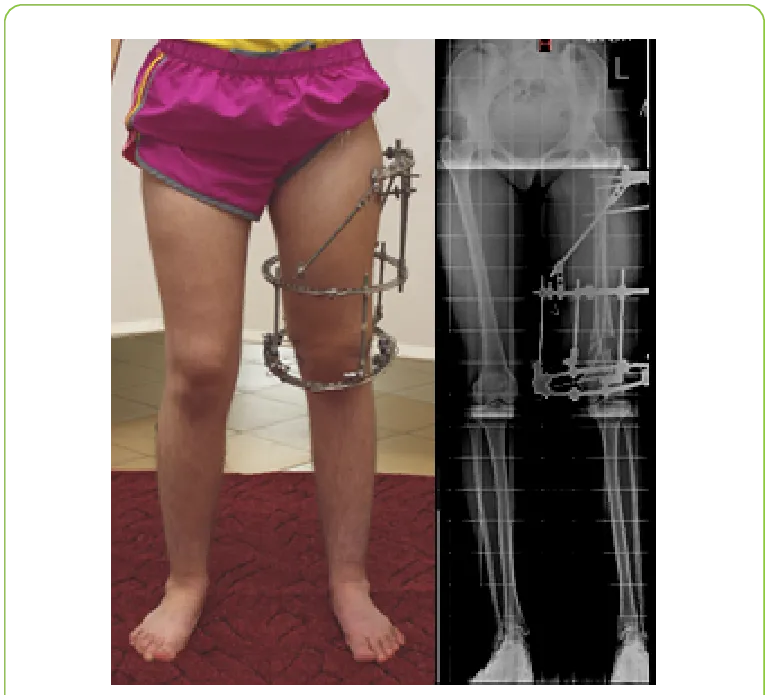

The Ilizarov technique uses a circular external fixator that applies gentle, controlled tension to bones. This stimulates natural bone regeneration (distraction osteogenesis), which allows bones to grow in length and correct deformities. It is widely used for hip, leg, and complex orthopedic reconstructions.

Recovery takes time and depends on the amount of correction needed. Most patients wear the frame for 4–8 months and continue physiotherapy. Normal walking without support usually resumes by 6–12 months.

Can you walk with an Ilizarov frame?

Yes. In fact, patients are encouraged to walk with support while wearing the Ilizarov fixator. Walking stimulates bone healing and prevents stiffness, although full weight bearing is increased gradually under the surgeon’s supervision.